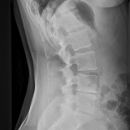

Halswirbelsäule lateral

Lagerung

aufrecht sitzend am Stativ

Arme seitlich hängend, aktiv nach unten ziehen lassen

Kopf gerade und Kinn leicht angehoben

Zentralstrahl

ZS senkrecht auf Objekt- und Detektormitte

Quer: 2 QF unter Kieferwinkel

Längs: ca. Processus mastoideus

Qualitätskriterien

Alle 7 HWK lateral dargestellt, orthogonale Darstellung der Grund- und Deckplatten, Processus spinosus des 7. HWK vollständig dargestellt, Mandibula überdeckt HWS nicht.